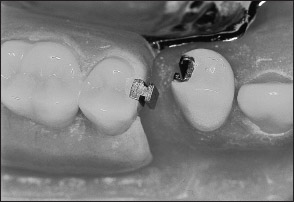

Unlike extracoronal retainers, intracoronal retainers are contained entirely within the contours of a clinical crown (Fig 1-4). Consequently, the use of intracoronal retainers generally requires the fabrication of two or more specially designed, complete-coverage crowns. In most instances, retention of intracoronal removable partial dentures is dependent upon exact parallelism of the retentive assemblies. Each assembly consists of two parts, commonly termed matrix (“female”) and patrix (“male”). Figure 1-5 illustrates the joining of a patrix and matrix to form a functional retentive unit. When a dislodging force is applied to the removable partial denture, binding occurs between the external walls of the patrix and the internal walls of the matrix. This binding results in retention of the prosthesis.

Fig 1-4 An intracoronal retainer lies within the contours of the clinical crown. An intracoronal retainer consists of a matrix or “female” component (right) and a patrix or “male” component (left).